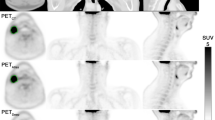

Tumour delineation

GTVs were automatically thresholded on each PET image using 40% of the maximum SUV [28] within a manual tumour volume contoured by an experienced consultant PET radiologist using RayStation. Primary and nodal volumes were delineated separately. Examples of the three PET images and automatic GTVs are shown in Fig. 2.

Example PET images reconstructed using the sCTAC (a), MRAC (b) and CTAC (c) attenuation correction maps. The threshold GTV contour is shown in purple, blue and red, respectively. Zoomed in pictures of the same GTVs are shown in (d). The patient was selected as having the sCTAC and MRAC \({\mathrm {SUV}}_{\max}\) differences closest to the mean differences